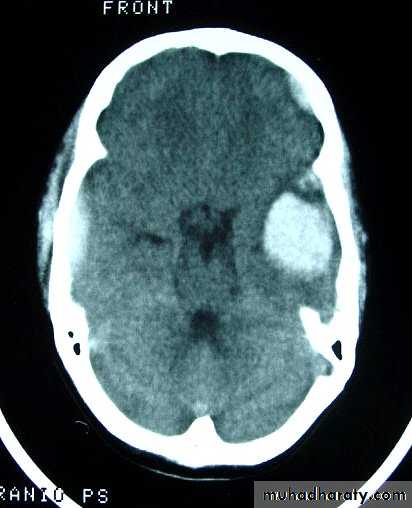

c. Intracerebral Haematoma

This is the least common of traumatic haematoma.

They are due to areas of traumatic contusion coalescing into a contusional haematoma.

Disrupted cerebral tissue release thromboplastins that potentiate haemorrhage.

CT scan: appear as hyperdence lesions with associated mass effect and midline shift.

Large intracerebral haematomas should be evacuated unless the patient’s neurological state is improving.

Small inracerebral haematomas may not require removal, but be aware that they can expand.